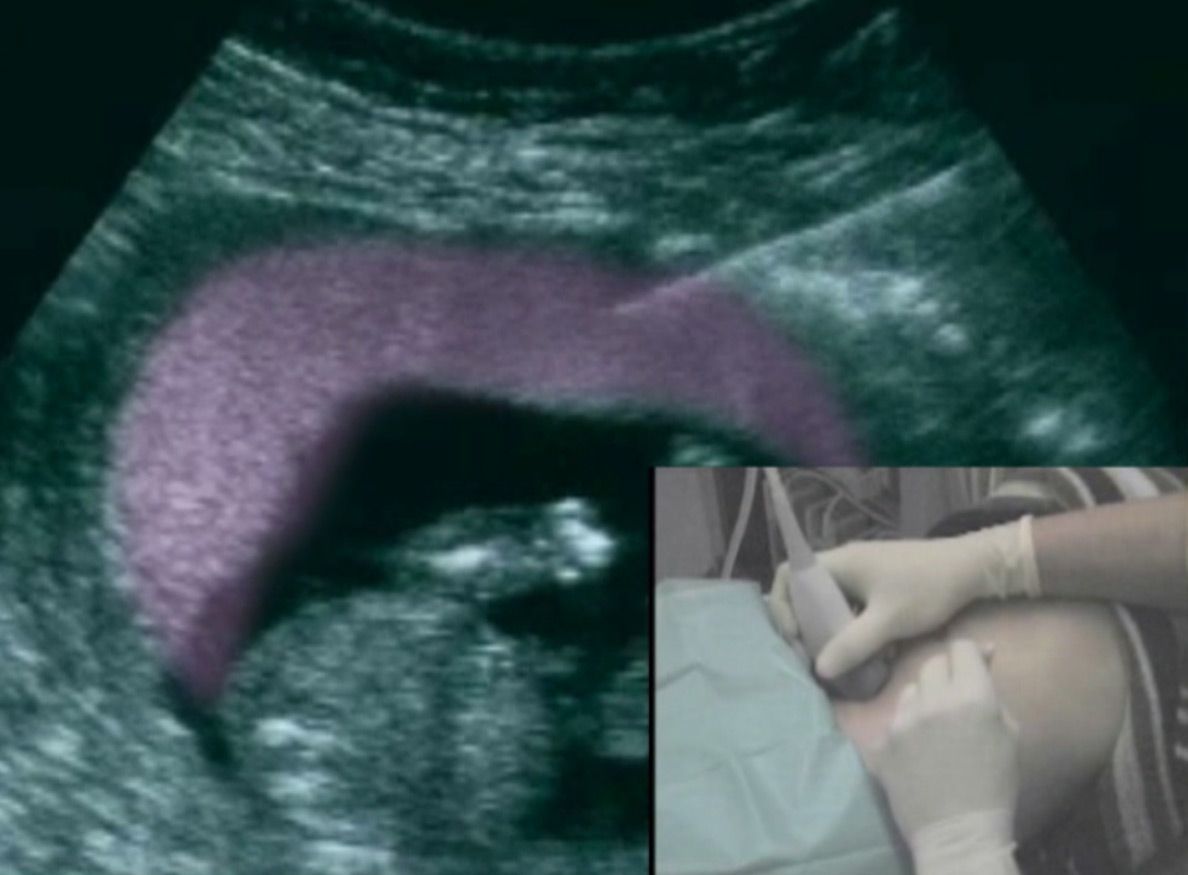

Mutterkuchenpunktion

Die Punktion erfolgt im Untersuchungszimmer. Zunächst die Bauchhaut desinfiziert und ein steriles Tuch über die Beine gelegt. Sie erhalten zunächst eine lokale Betäubung unter die Haut. Mit der eigentlichen Punktionsnadel wird dann eine Gewebeprobe aus dem Mutterkuchen gewonnen. Der Untersucher verfolgt den Verlauf der Nadel mittels Ultraschall und kann auf diese Weise die korrekte Position der Nadel bestätigen. Die Fruchthöhle wird nicht berührt. Nach korrekter Platzierung der Nadel im Mutterkuchen, wird eine Spritze mit einer Nährlösung aufgesetzt  und diese unter Sog zurückgezogen.

Die gesamte Punktion dauert etwa 1-2 Minuten und wird von den meisten Patientinnen als nicht schmerzhaft beschrieben. Insgesamt werden etwa 15g Chorionzotten gewonnen, die sich im Nährmedium befinden. Diese werden an Humangenetik zur weiteren Diagnostik weitergeleitet. Abschließend erfolgt nochmals eine Ultraschallkontrolle.